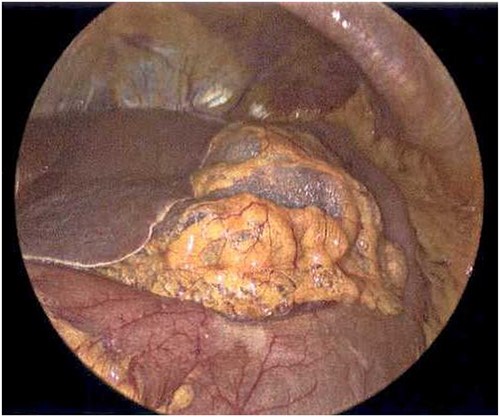

On Hospital Day 2, an interval CXR showed continued resolution of the right-sided pneumothorax but worsening subcutaneous emphysema of the bilateral chest wall and pneumoperitoneum (Fig. 3). Surgical consultation was sought, leading to diagnostic laparoscopy. In the abdomen, emphysematous changes within the gastrohepatic ligament and omental adhesions to the anterior abdominal wall were visualized (Figs 5 and 6). Laparoscopic exploration revealed no diaphragmatic injury or perforated viscera but identified emphysematous changes throughout the preperitoneal space, small and large bowel mesentery, and right paracolic gutter (Figs 7 and 8). Immediate post-op CXR no longer showed evidence of pneumoperitoneum (Fig. 4). The patient was transferred back to the ICU and extubated after three days on Day 5. After the removal of chest tube and transfer to a medical floor on Day 8, the patient developed aspiration pneumonia that was treated with antibiotics. She was discharged on Day 15.

Laparoscope of the anterior abdominal wall revealing emphysematous changes within the preperitoneal space.